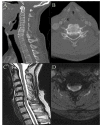

Purpose: The preoperative medical clearance process is well established to screen for medical comorbidities and therefore must be thorough. However, screening for potential cervical spine disease is often overlooked. In older surgical candidates, the presence of cervical spondylosis can increase risk of iatrogenic cervical spine injury during prolonged neck extension in non-spinal surgeries. We present a standard protocol for cervical spine clearance and a novel sustained neck extension maneuver through a retrospective case series.

Methods: Sixty-three consecutive cases that underwent preoperative cervical clearance between April 2012 and December 2019 were reviewed. Referral for clearance occurred through the department of anesthesiology after concerning radiographic or physical exam findings were noted. A standard preoperative screening protocol with a sustained one-minute neck extension maneuver was implemented. Recommendations were made for standard neck precautions with or without neuromonitoring or for cervical spine decompression surgery prior to the planned procedure.

Results: There were 25 patients with symptoms of myelopathy, 11 with radiculopathy and 13 with neck pain at baseline. Cervical spondylosis was observed in 51 patients, cervical canal stenosis in 29 and cervical myelomalacia in six. Fifty-seven patients underwent neck extension exam and 25 exhibited new or worsening symptoms. Myelopathic symptoms and radicular pain at baseline and positive Hoffman's and Spurling's sign, independently, were significantly associated with a positive neck extension exam (p<0.05). Fourteen patients were recommended for cervical decompression prior to planned procedure.

Conclusions: Our preoperative cervical spine clearance protocol is safe and may aid in identifying patients susceptible to iatrogenic cervical spine injury.